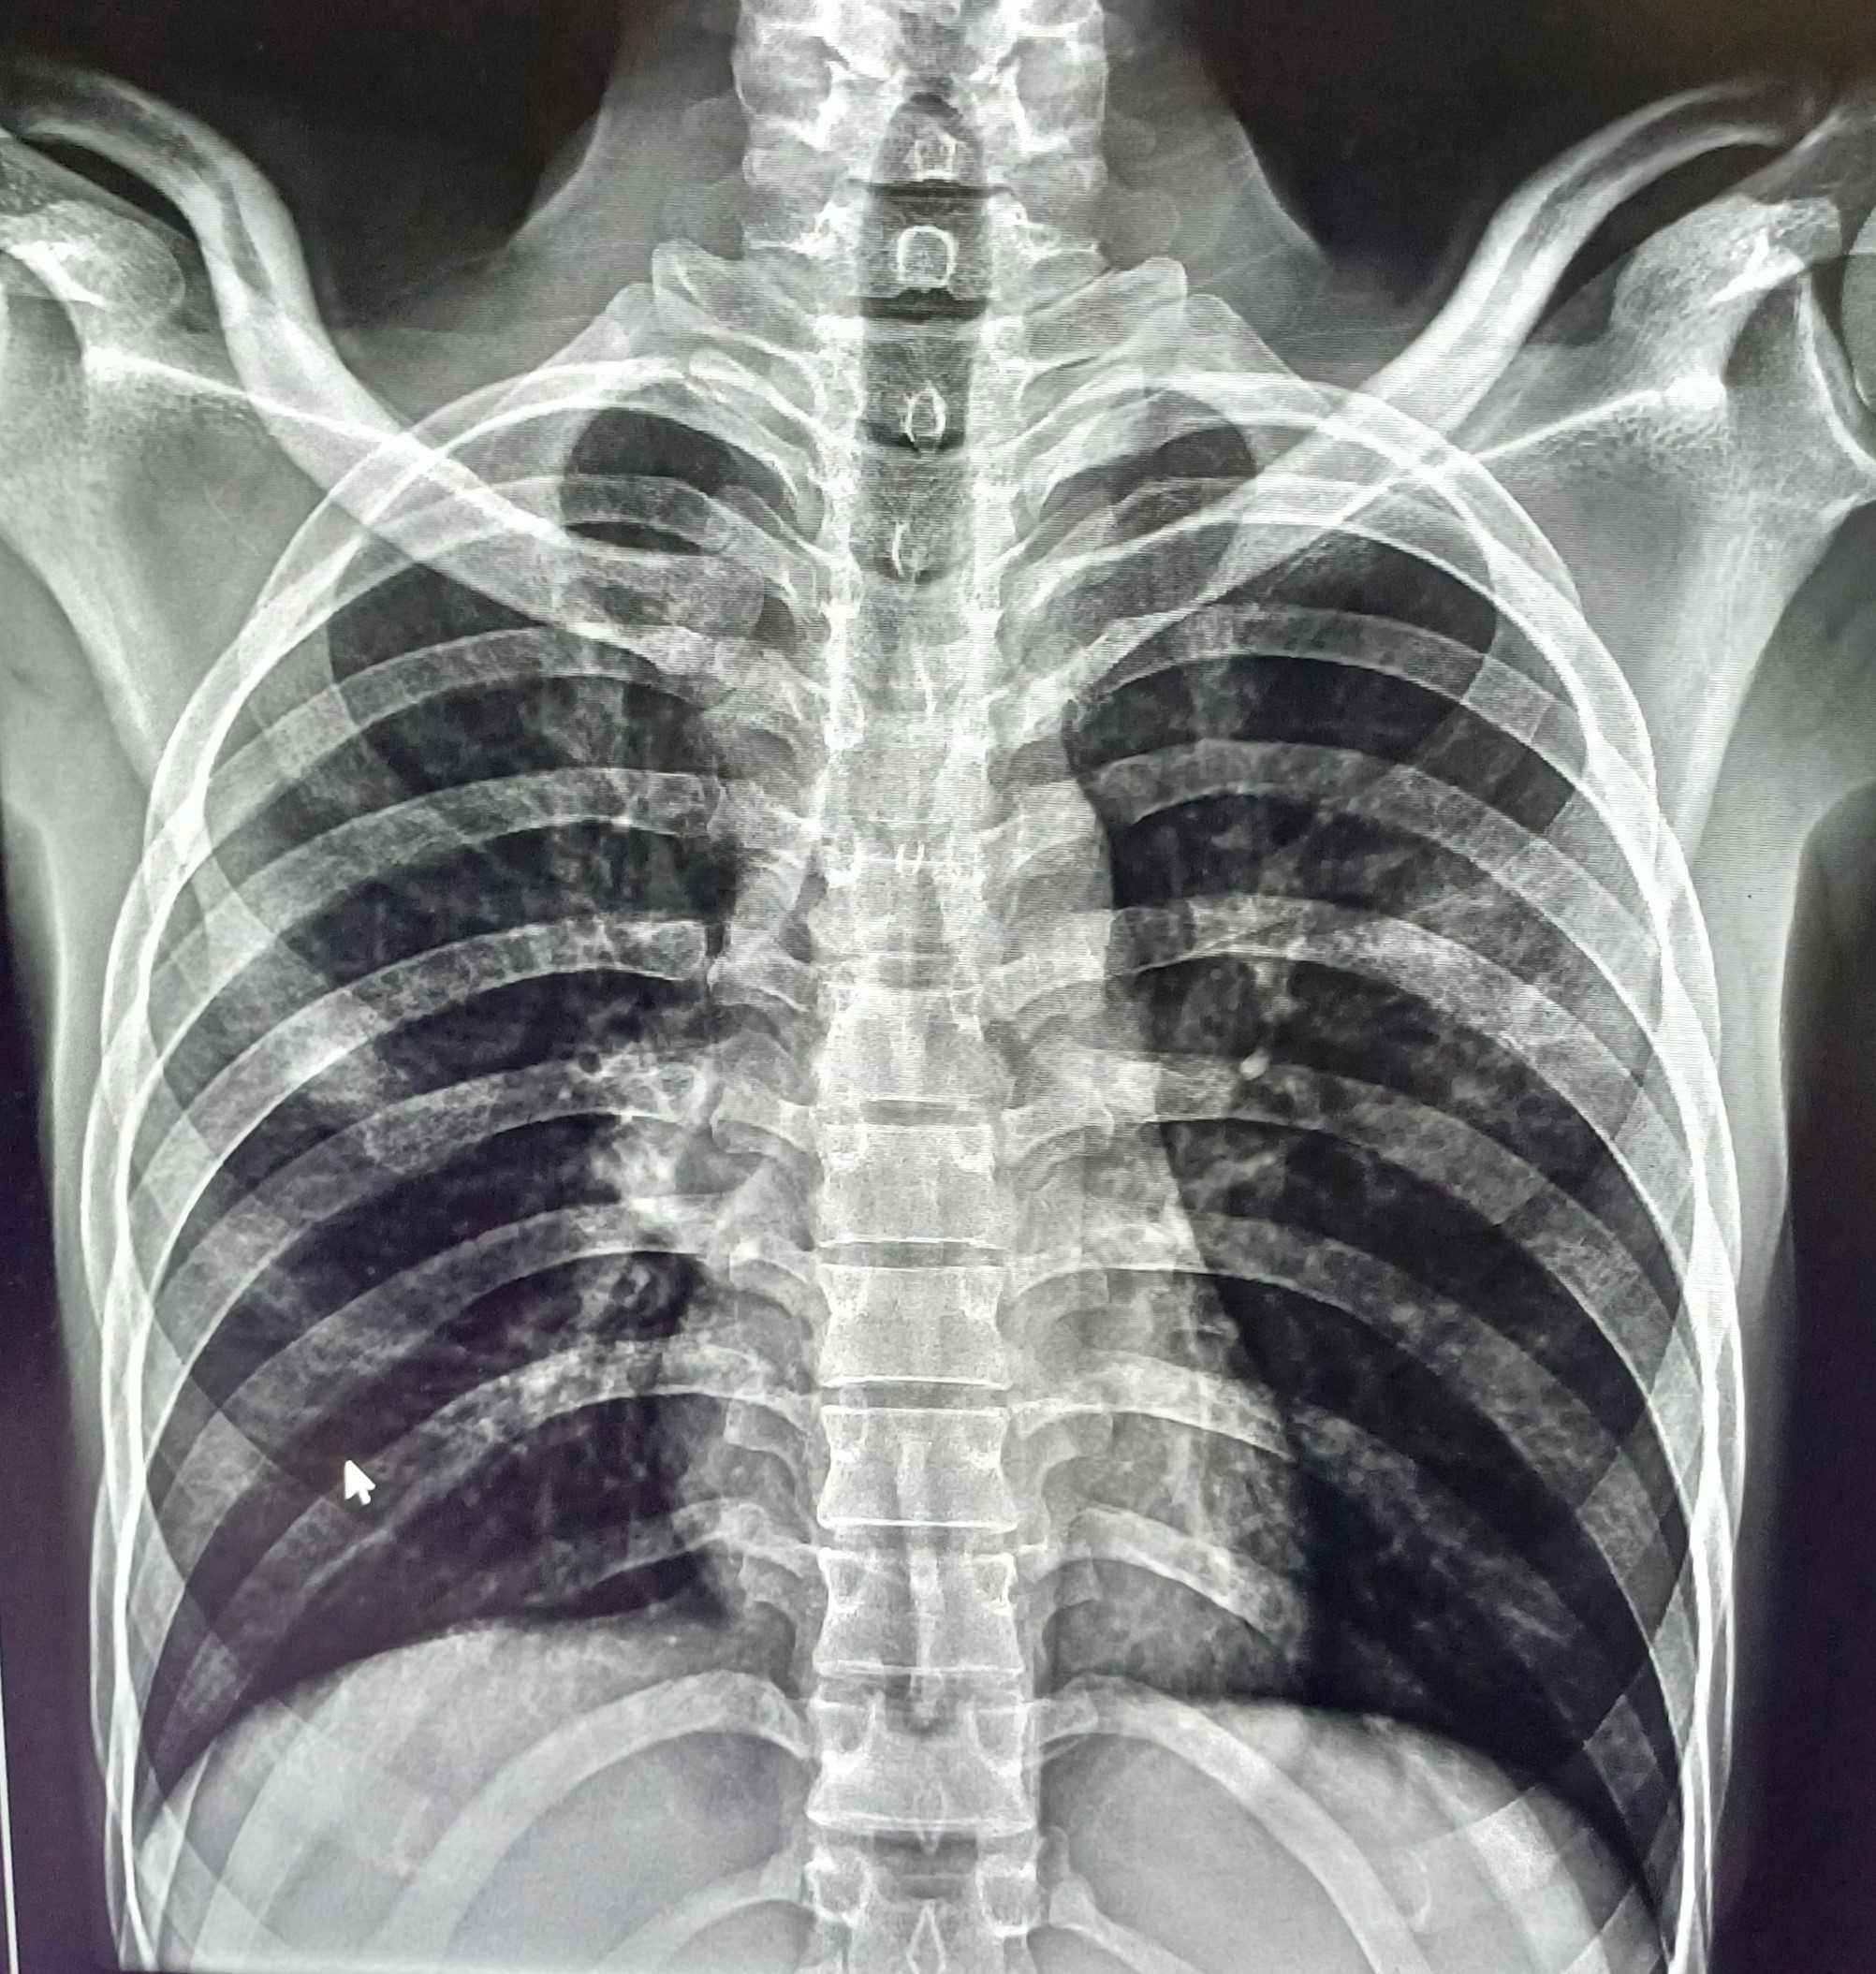

| 68 | IGGMC, Nagpur, Nagpur | P2 | 29-4404 | Gaurav Wankhede | Consent taken on Paper | 19 Yrs. |

Provisional Diag : Pulmonary Tuberculosis

Final Diag : TB Infiltration |

TB Case (Confirmed) | Bilateral Upper Zone & Mid Zone TB Infiltration | Abnormality visible on x-ray |